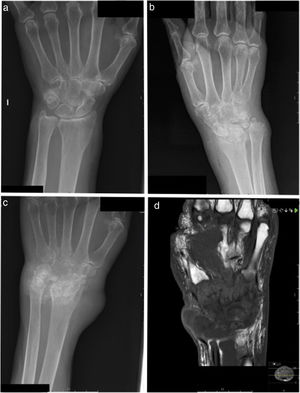

(A) Normal X-ray. (B) X-ray of bone showing polyarthritis at the carpus and radiocarpal joint; joint with synovial calcifications. (C) Follow-up bone X-ray eight months after image B; progression of joint damage can be seen, with bone involvement suggesting osteomyelitis. (D) Magnetic resonance imaging. T1-weighted image with contrast shows widespread severe damage in all carpal bones, distal ulna and radius and second to fifth metacarpals, as well as synovial thinning in all carpal joints, with a heterogeneous fluid collection on the dorsal aspect of the wrist.

This was a 74-year-old woman from Galicia with no history of travel abroad who lived in a rural environment, but had no domestic animals. Three years previously she had been diagnosed with seronegative rheumatoid arthritis after an episode of oligoarthritis, treated with methotrexate (22.5 mg/week) and prednisone (10 mg/day). Since the onset of the disease, the patient had suffered from discomfort, mainly in the left wrist, with an initially normal X-ray (Fig. 1A). She consulted for pain and swelling of the left wrist, and X-ray showed polyarthritis of the carpus and radiocarpal joint (Fig. 1B); etanercept (50 mg/week) was added to her treatment, with clinical improvement. Eight months later the patient was admitted for arthritis of the left wrist with spontaneous discharge of exudate; she had not previously had infiltration and had not suffered trauma. Her C-reactive protein (CRP) was 1.7 mg/l, with an erythrocyte sedimentation rate (ESR) of 6 mm/h. X-ray (Fig. 1C) and arthrocentesis were performed, with release of purulent fluid; there was no bacterial or fungal growth in cultures and she was treated empirically with levofloxacin (500 mg/day) and rifampicin (600 mg/day). Three weeks later, she was readmitted for a large swelling on her wrist with purulent drainage through three fistulas. MRI (Fig. 1D) showed severe involvement of the carpal bones, with heterogeneous fluid collection on the dorsal aspect; antibiotic therapy was discontinued and surgical debridement was performed with release of caseous material. In all intra-surgical specimens the auramine stain was positive, with the presence of acid-fast bacilli. Molecular detection of the genome of Mycobacterium tuberculosis complex was performed (Cepheid Xpert MTB/RIF, USA). The result was negative; suspected MNT infection was treated with rifampicin (150 mg)/isoniazid (75 mg)/pyrazinamide (400 mg)/ethambutol (275 mg; 3 tablets/day), linezolid (600 mg/12 h) and levofloxacin (500 mg/24 h). Three weeks later, Mycobacterium malmoense grew in all the samples, with identification by Genotype Mycobacterium CM/AS (Bruker, Germany), subsequently confirmed by sequencing (rpo®). Antibiogram (Sensititre SLOMYCO, Thermo Fisher, Germany) showed resistance to isoniazid and streptomycin and sensitivity to rifampicin, ethambutol, clarithromycin, moxifloxacin and amikacin. The treatment was changed to rifampicin (450 mg/24 h) and ethambutol (800 mg/24 h). The patient required further surgical cleaning of the wound on two more occasions and made good progress. She attended a check-up six months after starting treatment, with no inflammatory findings on examination, and continued treatment with rifampicin and ethambutol. Follow-up was subsequently lost due to the patient's death from causes unrelated to the infection.